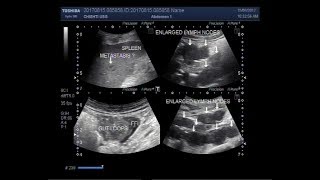

Ultrasound Video showing enlarged abdominal lymph nodes with ascites and a metastasis in spleen.

This video shows enlarged abdominal lymph nodes with ascites and a metastasis in spleen.